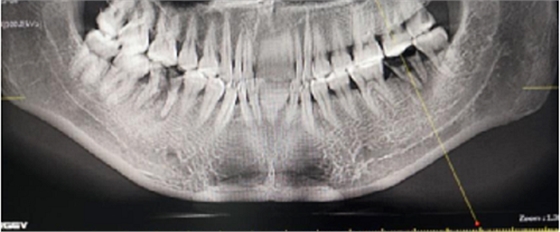

左側(cè)下頜第二磨牙及右側(cè)下頜第一磨牙同時(shí)即刻種植病例?;颊吣贻p女性,無系統(tǒng)性疾病。37及46殘冠及殘根,且46劈裂,無法冠修復(fù),必須拔除。37根尖慢性炎癥,大量肉芽組織存在,46根分叉較高,根分叉骨質(zhì)尚可。CBCT示:根尖骨質(zhì)至下牙槽神經(jīng)管距離可滿足種植體的初期穩(wěn)定性,遂考慮即刻種植,并在種植體周邊填入骨粉并覆蓋骨膜,雙側(cè)的種植體初期穩(wěn)定性相差無幾,但考慮到37根尖慢性炎癥較大,遂給予埋入式種植。

患者左側(cè)16慢性根尖周炎,17缺失。16根尖炎癥距上頜竇底較近,需內(nèi)提升,但是因?yàn)閮?nèi)提升后骨質(zhì)較薄所致植入深度過深,埋入式植入。17非埋入式種植。后期效果均可。